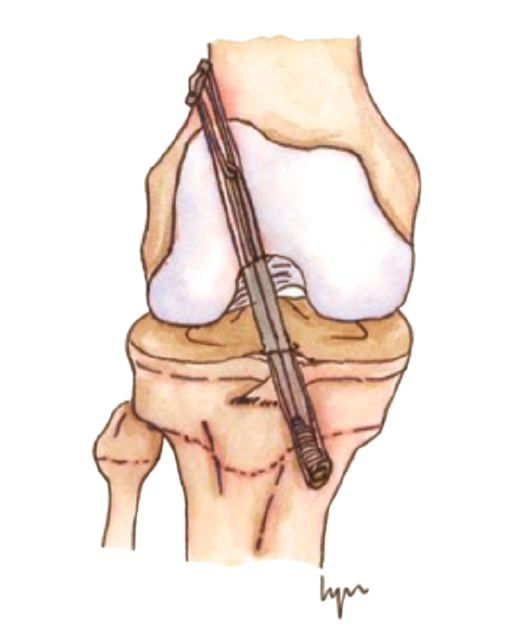

El tratamiento conservador, mediante reposo deportivo y rehabilitación, con una incorporación gradual a la práctica deportiva, pretende recuperar la actividad previa evitando las posibles lesiones fisarias iatrogénicas asociadas a las técnicas de reconstrucción del LCA convencionales, que pudieran producir dismetrías y alteración de los ejes(4,5,6,7,8). Sin embargo, este enfoque subestima las posibles lesiones meniscales y condrales futuras relacionadas con la inestabilidad secundaria. Por otro lado, el tratamiento quirúrgico intenta prevenir estas lesiones meniscales y condrales, secundarias a la inestabilidad que se produce tras la lesión del LCA, asumiendo el riesgo potencial de lesiones fisarias. Atendiendo a estas premisas, en los últimos años se han descrito técnicas específicas para pacientes esqueléticamente inmaduros que minimizan la agresión de la placa fisaria(9,10,11,12,13,14,15,16)(Figura 1).

Figura 1. Esquema de los tipos de reconstrucción del ligamento cruzado anterior (LCA) según la relación con la fisis. A: epifisaria; B: transfisaria.

Las técnicas de “ahorro fisario” o physeal sparing

Estas técnicas evitan la agresión de la placa fisaria. Una de las primeras fue descrita por MacIntosh y Darby(11), y modificada posteriormente por Micheli(68), conocida como la técnica de la “cintilla iliotibial” (illiotibial band –ITB–). Utiliza parte de la cintilla iliotibial como autoinjerto, dejando su porción distal unida al tubérculo de Gerdy. Es una técnica no anatómica, extra-intraarticular, en la que el injerto se pasa alrededor y por detrás del cóndilo femoral externo, en la posición over-the-top, a través de la escotadura y, posteriormente, por debajo del ligamento intermeniscal para, finalmente, fijarlo en el periostio de la tibia distal a la fisis.

Figura 4. Técnica transepifisaria o todo epifisaria.

Desde el punto de vista biomecánico, esta técnica proporciona una mejor estabilidad anteroposterior y rotacional en comparación con las técnicas de reconstrucción “todo epifisaria” y “transtibial over-the-top”, aunque se ha observado que puede aumentar la constricción del compartimento externo con la rotación en ciertos grados de flexión(70)(Figura 3).

Otra de las técnicas de ahorro fisario es la llamada all epiphyseal. La primera de estas técnicas fue descrita por Anderson(13)(Figura 4) y está indicada en pacientes en estadio de Tanner I, II o III. Se realiza evitando la invasión de la fisis por parte de los túneles, utilizando injerto cuadrifascicular de isquiotibiales, que son estabilizados en el fémur mediante un sistema de tenosuspensión cortical y en la tibia con un tornillo interferencial distal a la fisis (Figura 5). Los resultados en un grupo de 12 pacientes fueron buenos, pero refieren que la técnica es compleja y demandante para un cirujano no experto en rodilla. Esta técnica minimiza el daño fisario, es anatómica y reproduce la isométrica(71). Se ha descrito la aparición de una deformidad angular relacionada con una epifisiodesis secundaria por sobretensionado de la plastia. En la actualidad, se han descrito multitud de modificaciones de esta técnica(15,72,73,74)(Figura 6).